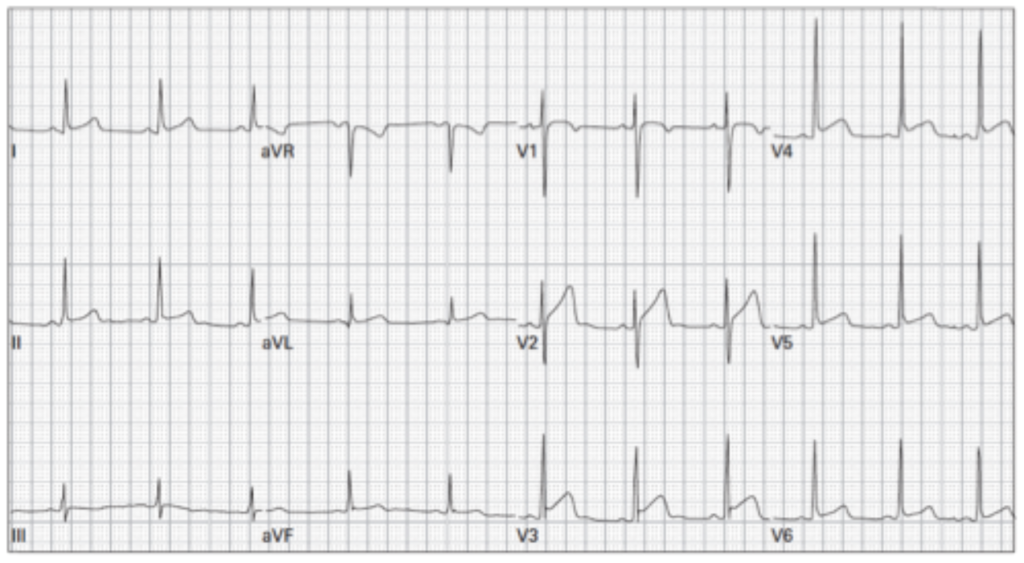

Masculino de 24 años, sano con dolor torácico. Usted decide llamar al cardiólogo hemodinamista, quien luego de valorar el paciente y el electrocardiograma indica que no lo llevará a realizar cateterismo. ¿Qué datos morfológicos en este electrocardiograma habrá considerado para tomar la decisión?